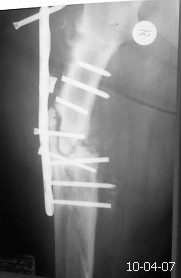

[Ortho] ложный сустав бедра

Уважаемые коллеги. Просьба помочь с тактикой лечения данной пациентки. Травма в 2007 г.

лечили больную консервативно. В 2009 г. у нас остеосинтез пластиной в сочетании с костной

аутопластикой. Со слов больной после операции, дома в течение 6-ти месяцев соблюдала

постельный режим,после чего начала ходить. Больная повышенного питания, сахарный диабет

2-го типа, неопрятна. Фотографию прилагаю. Планируем выполнить реостеосинтез пластиной с

угловой стабильностью с повторной аутопластикой и пластикой по Хахутову. У кого какие

мнения по поводу лечения?